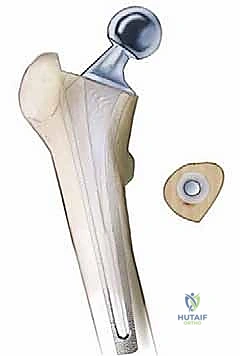

إن مفصل الورك الصناعي يُعد أحد أعظم الإنجازات الطبية في القرن العشرين، وهو حل رائع لملايين الأشخاص الذين يعانون من آلام الورك المبرحة الناتجة عن الخشونة أو الروماتيزم. لكن، مثل أي جهاز ميكانيكي مزروع في جسم الإنسان، قد يحتاج إلى مراجعة وتغيير بمرور الوقت. عندما تكون مكونات المفصل الصناعي (سواء الكأس الحُقّي أو الساق الفخذية) قد اندمجت بقوة مع عظم المريض، فإن إزالتها لا تتم ببساطة، بل تتطلب تقنيات جراحية متقدمة للغاية، وأدوات خاصة، للحفاظ على "مخزون العظام" الحيوي المتبقي وحماية الهياكل العصبية والوعائية المجاورة.

- القناة الفخذية (Femoral Canal): التجويف الأنبوبي داخل عظم الفخذ حيث يتم إدخال الساق الصناعية. في حالات المراجعة، قد يتغير شكلها بسبب الاسترخاء أو التآكل، مما يتطلب سيقانًا صناعية خاصة (طويلة ومغطاة بمسام دقيقة).